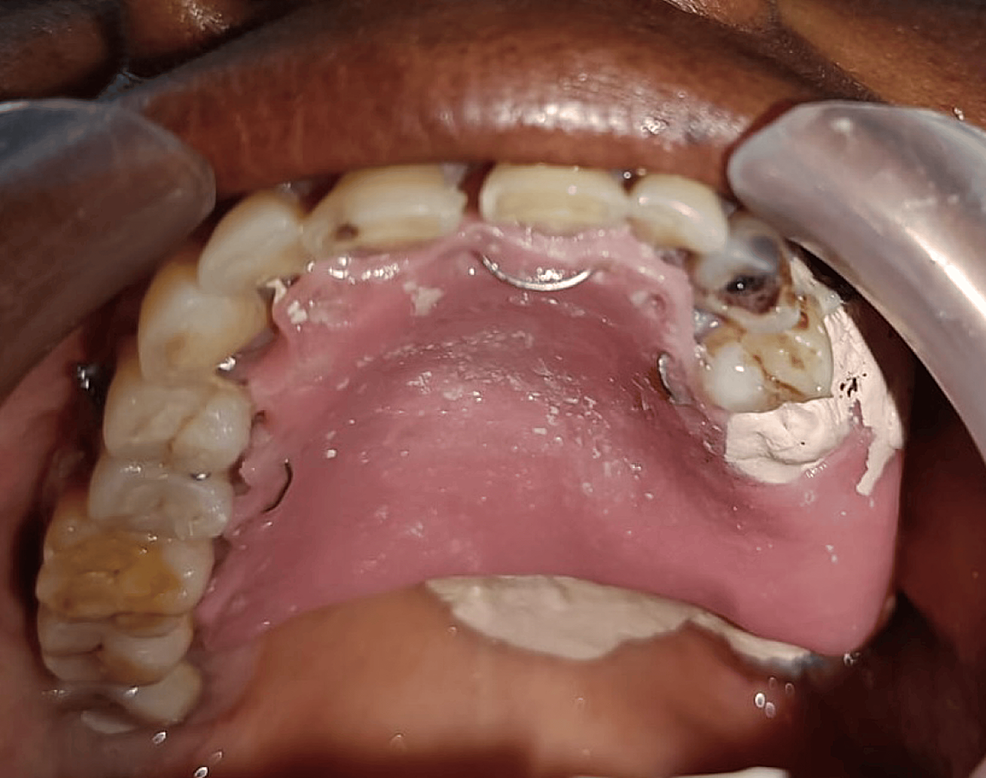

What Is Palatal Obturator . Web the obturators are prosthesis used to close palatal defects after maxillectomy, to restore masticatory. Web ️ download dr teeth apps using these links:android users:. Web a palatal obturator is a prosthesis that closes defects in the roof of the mouth. Web a palatal obturator is a prosthesis that totally occludes an opening such as an oronasal fistula (in the roof of the mouth). Web what is a palatal obturator? Web an obturator is a device that fills the surgical defect after a maxillectomy or palatectomy and restores the function of swallowing,. Web a soft palate obturator (also known as a speech and feeding aid/device) replaces the missing piece (s) of muscle (s) and fills. It can improve speech, air flow, eating, and.

Web an obturator is a device that fills the surgical defect after a maxillectomy or palatectomy and restores the function of swallowing,. It can improve speech, air flow, eating, and. Web a soft palate obturator (also known as a speech and feeding aid/device) replaces the missing piece (s) of muscle (s) and fills. Web ️ download dr teeth apps using these links:android users:. Web a palatal obturator is a prosthesis that totally occludes an opening such as an oronasal fistula (in the roof of the mouth). Web a palatal obturator is a prosthesis that closes defects in the roof of the mouth. Web what is a palatal obturator? Web the obturators are prosthesis used to close palatal defects after maxillectomy, to restore masticatory.

What Is Palatal Obturator Web an obturator is a device that fills the surgical defect after a maxillectomy or palatectomy and restores the function of swallowing,. Web what is a palatal obturator? Web an obturator is a device that fills the surgical defect after a maxillectomy or palatectomy and restores the function of swallowing,. Web the obturators are prosthesis used to close palatal defects after maxillectomy, to restore masticatory. Web a palatal obturator is a prosthesis that totally occludes an opening such as an oronasal fistula (in the roof of the mouth). It can improve speech, air flow, eating, and. Web ️ download dr teeth apps using these links:android users:. Web a soft palate obturator (also known as a speech and feeding aid/device) replaces the missing piece (s) of muscle (s) and fills. Web a palatal obturator is a prosthesis that closes defects in the roof of the mouth.